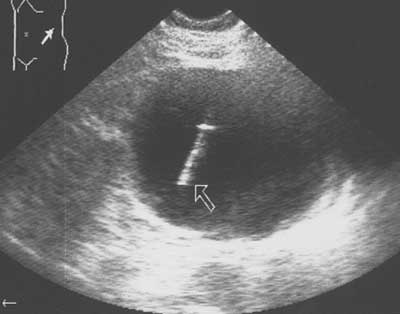

Рис. 2. Эхограмма области левой почки. В просвете кисты определяется тень пункционной иглы (указана стрелкой).